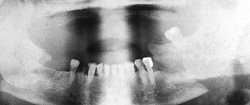

Osteosynthesis procedures are performed at our clinic according to modern international standards. Mini and micro plates made of titanium and special medical steel are used to stabilize the fractured bones. Especially for the treatment of temporomandibular joint fractures a joint plate was developed in our clinic. The development and application of resorbable osteosynthesis materials is at the same time a research task of the clinic.